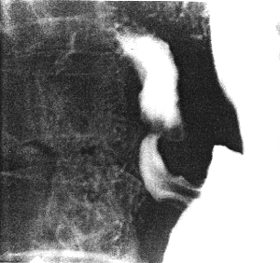

Case 28.1. G.G., 52 year old male. Radiographic examination showed a moderate degree of constant contraction of the pyloric sphincteric cylinder, with absence of normal, cyclical contraction and relaxation; the contraction fixed the pyloric aperture in the open position (Fig. 28.1). The stomach appeared to be hypertonic; rapid emptying of fluid barium occurred. Endoscopic biopsy of the "antral" region revealed acute on chronic gastritis; no evidence of malignancy was seen. Repeat endoscopic biopsy two months later showed acute on chronic inflammatory reaction in the lamina propria, with eosinophylic infiltration and without evidence of intestinal metaplasia. Stainings for Helicobacter pylori were positive. A third endoscopic biopsy two months after the second, showed chronic gastritis with intestinal metaplasia. Stainings for Helicobacter pylori were negative.

| Fig. 28.1. Case G.G. Moderate degree of constant contraction of pyloric sphincteric cylinder (arrows). Cyclical activity absent. Pyloric aperture patent |